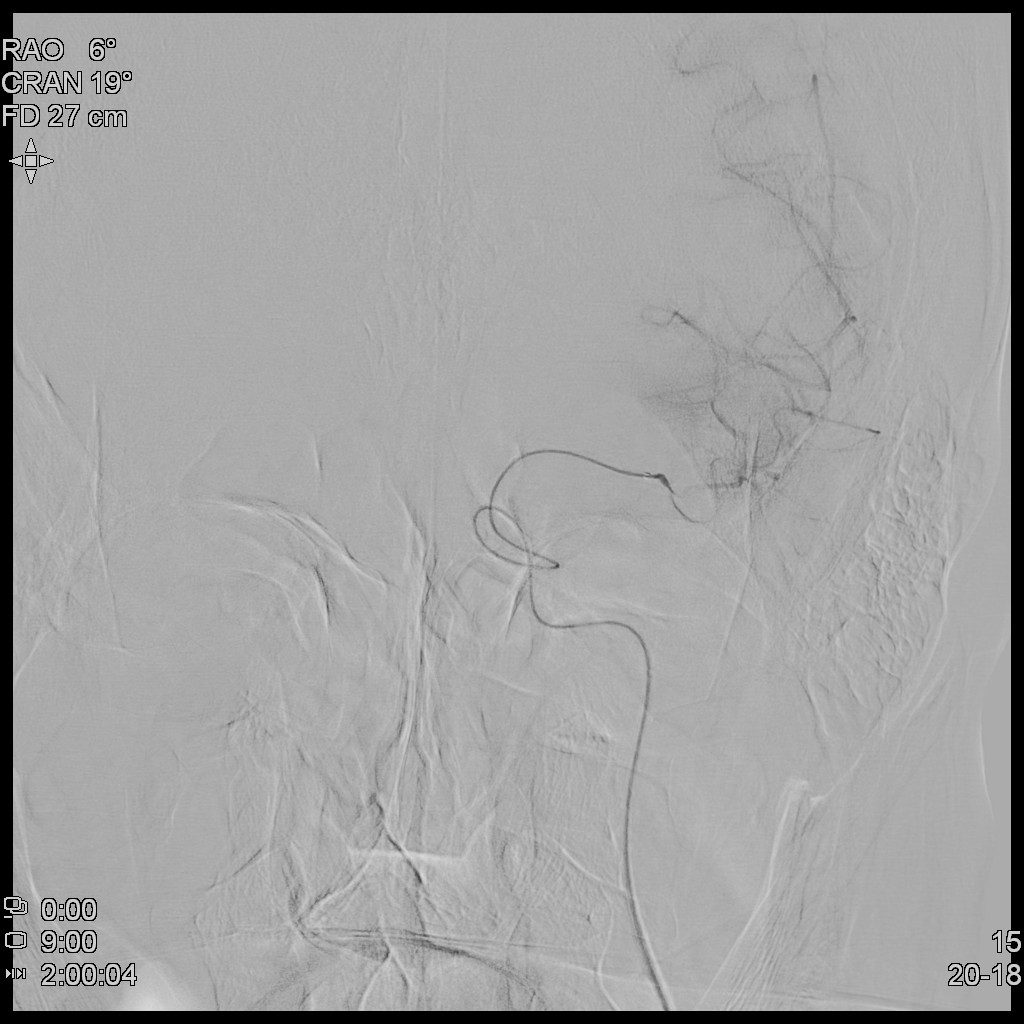

때문에 TFCA(Trans-Femoral Cerebral Angiography)를 통해 환자 뇌혈관의 막힌 혈관을 뚫어보고자 하였고, 환자는 1시간여만에 뇌혈관조영술을 시행하게 되었다.

뇌혈관조영술(TFCA)을 통해 어느정도 막힌 혈관의 일부를 뚫어내고 이후 혈류가 전달되는 모습을 확인하였다.

하지만, 환자가 병원에 시점은 뇌졸중이 발생한 지 상당히 시간이 지난 것으로 생각되었다.